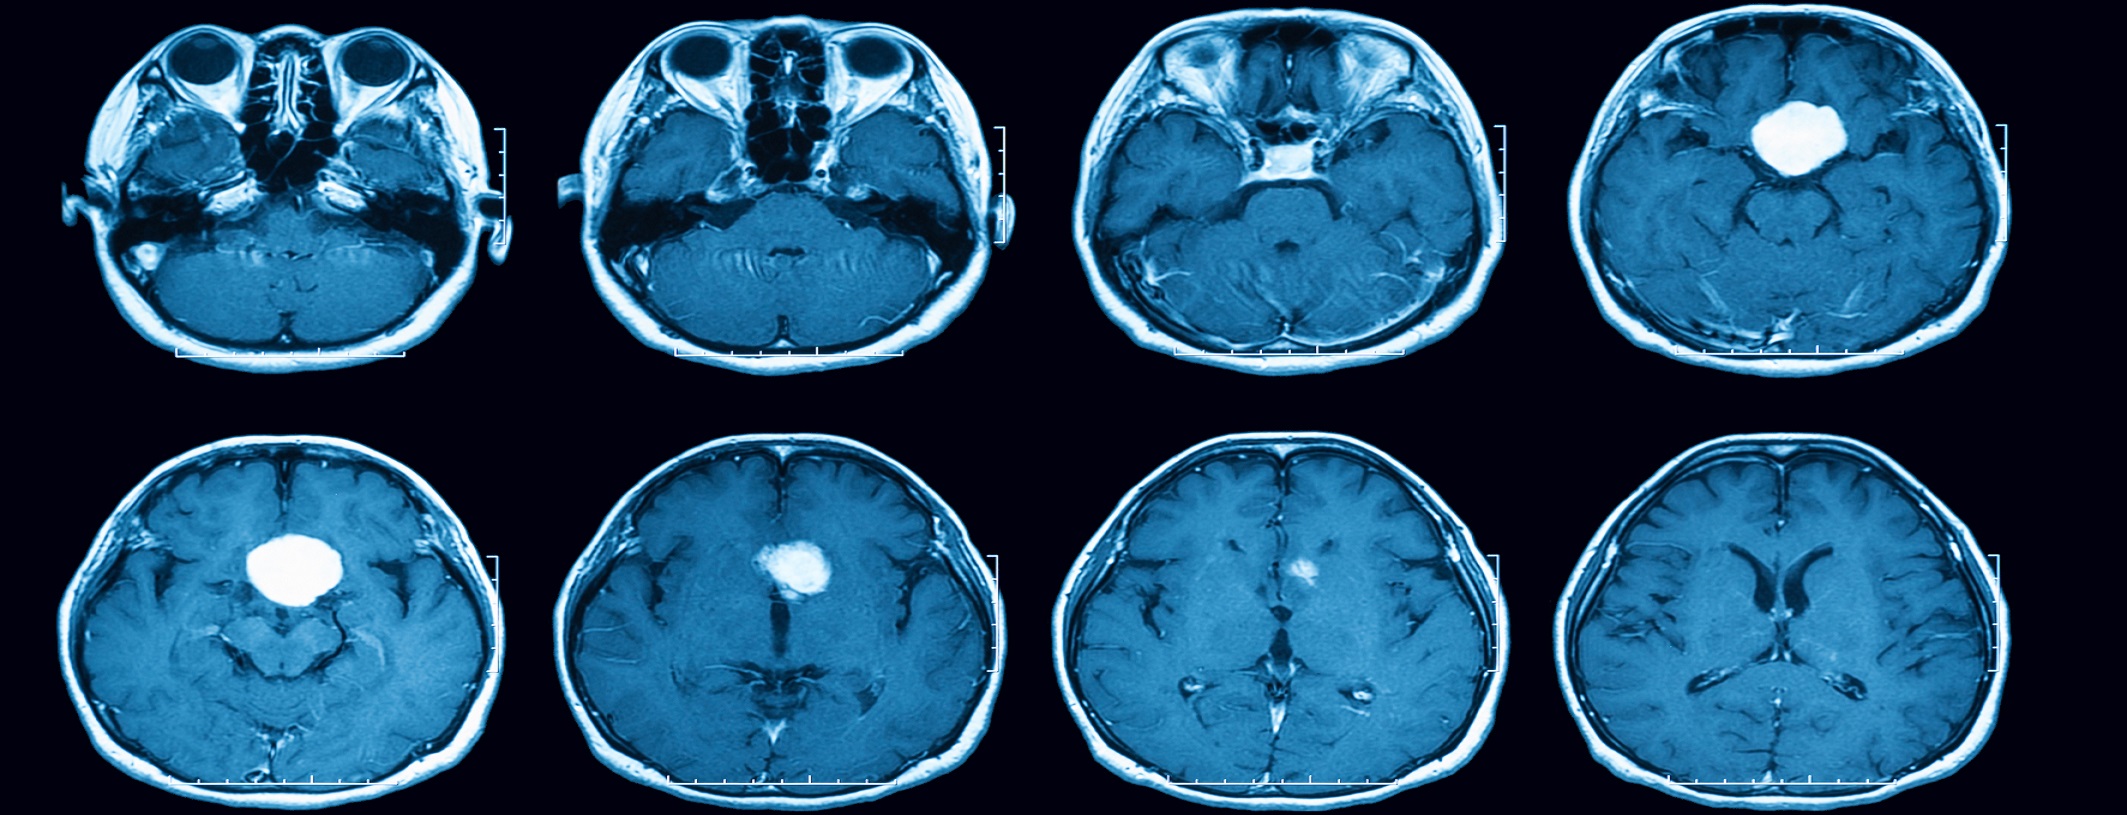

Magnetic resonance imaging (MRI) scan of the brain with gadolinium (GD) contrast medium injections , transverse view, case of pituitary mass